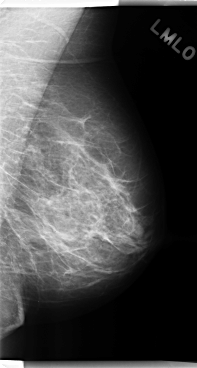

C_0252_1.LEFT_MLO

LEFT_MLO LINES 4784 PIXELS_PER_LINE 2552 BITS_PER_PIXEL 12 RESOLUTION 50 NON_OVERLAY